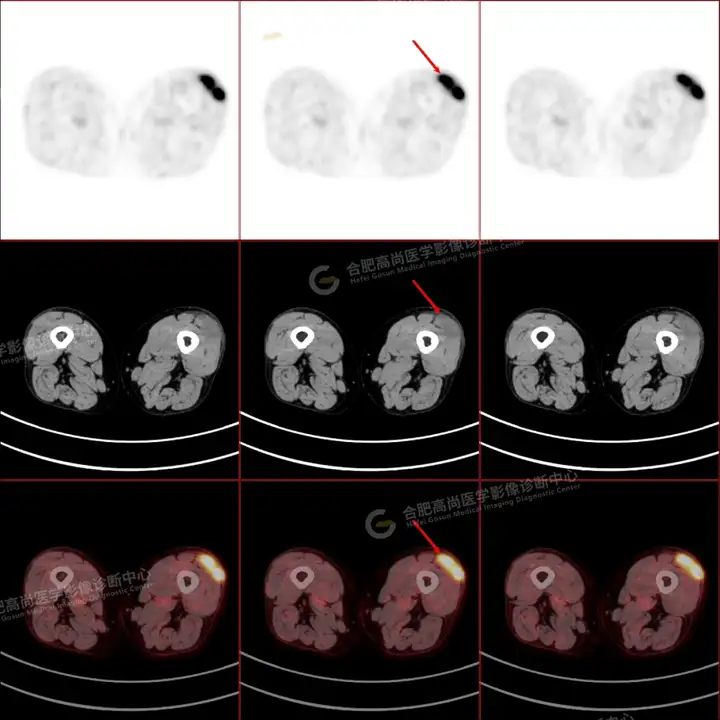

PETCT检查所示:图1、3-17全身多处(双上臂、胸背部、左侧乳腺、左侧腰部、腹壁、双侧臀部及双侧大腿)皮肤下结节及肿块样软组织密度灶,FDG代谢不同程度增高,双侧颈部、左侧锁骨区、纵隔内(1区)及双侧腋窝多发肿大淋巴结,FDG代谢明显增高,符合皮肤来源淋巴瘤。

图2右侧颈部包块切除术后,右侧锁骨区术区皮下片状密度增高灶,FDG代谢异常增高,考虑术后炎性反应。